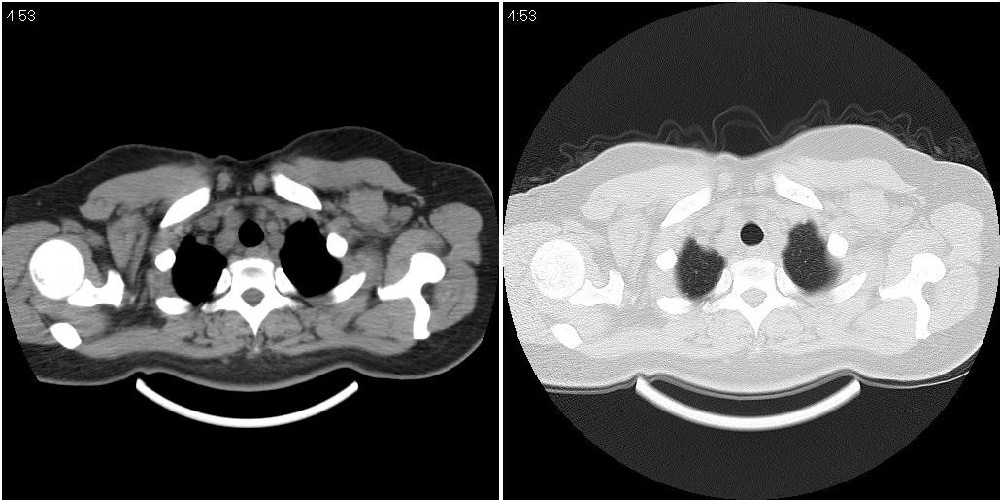

标题: CT24795:女性,47岁,右下腿静脉静脉曲张手术前体检,发现 [打印本页]

标题: CT24795:女性,47岁,右下腿静脉静脉曲张手术前体检,发现

囊性无明显占位效应:1淋巴管囊肿2畸胎瘤(其上部见小钙化)3前肠囊肿

右上纵隔囊性占位性病变;考虑淋巴管囊肿,不排除支气管囊肿。

支气管囊肿、囊性畸胎瘤、肠源性囊肿均有可能。

右上纵隔囊性占位性病变;考虑淋巴管囊肿,不排除支气管囊肿。 建议增强。

考虑淋巴管囊肿,不排除前肠囊肿。